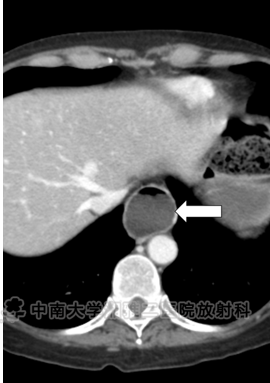

● 对比增强CT显示食管明显扩张(箭头所示)。

● 硬皮病:这是诊断,由食管扩张、粪便滞留、便秘史、结肠囊样积气、小肠皱襞表明。

● 本病例的影像学表现和便秘的临床史强烈提示了硬皮病的诊断,或进行性系统性硬化症。